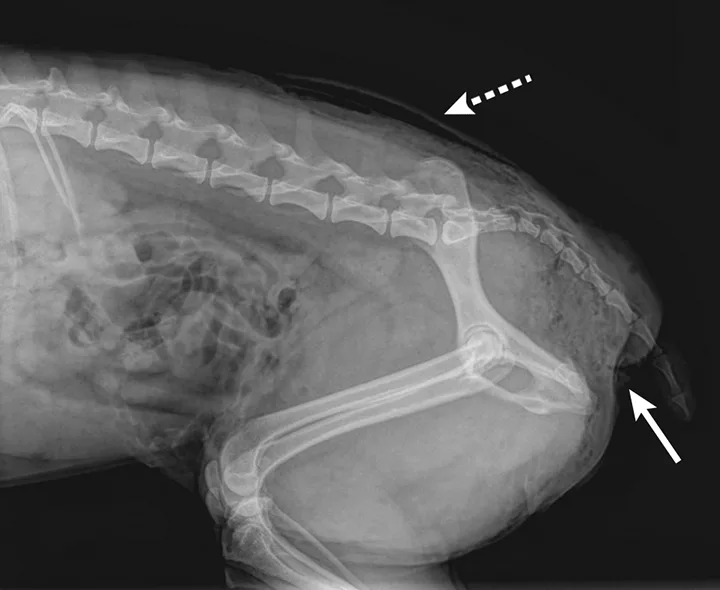

An x-ray of dog’s neck area with patches of radiolucent air in the soft tissue and in the cranial mediastinum.

Perineal subcutaneous emphysema (solid arrow). Bites near the tail should be inspected for nerve injury and rectoanal damage. Subcutaneous emphysema can also be seen in the dorsocaudal area (dashed arrow).